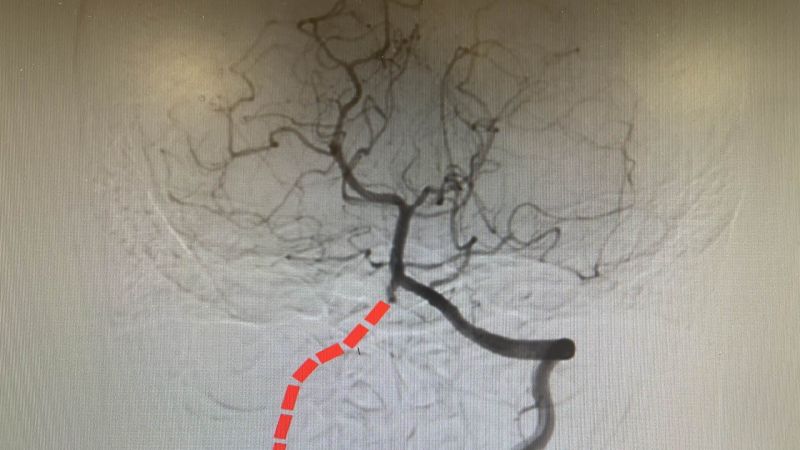

为寻求进一步治疗,家属慕名来到四川泰康医院神经外科苑玉清教授门诊。苑主任仔细分析病史及影像资料后,高度怀疑宁宁的“椎动脉闭塞”是导致症状的主因。入院后,医疗团队予以宁宁行头颅灌注磁共振检查发现有右侧小脑及脑干广泛血流灌注减少,随后安排完善DSA,最终确诊为“右侧椎动脉及右小脑下后动脉闭塞”。由于宁宁症状明显,保守治疗无效,手术成为最佳选择。

3月25日,由苑玉清主任主刀,为宁宁实施“枕动脉血管搭桥-枕肌贴敷术”。该手术通过在颅骨外游离血管、剥离部分枕肌,并将其血管与小脑表面血管吻合,建立新的侧支循环,从而改善因椎动脉闭塞所导致的脑组织缺血状况。

“手术需要在显微镜下精细操作,由于小脑浅表动脉难以适配,只有施行手术的第二套方案:分别将带蒂脑膜及头夹肌与脑干延髓及小脑后下严密贴敷,使肌肉及脑膜供血与相应缺血区关联吻合,以实现中长期增生性血管供血。由于小脑长期缺血,脑组织非常脆弱,稍有不慎就可能导致梗死加重或水肿、出血而致吻合失败。”苑主任介绍说,整个手术历时约4小时,过程非常顺利。